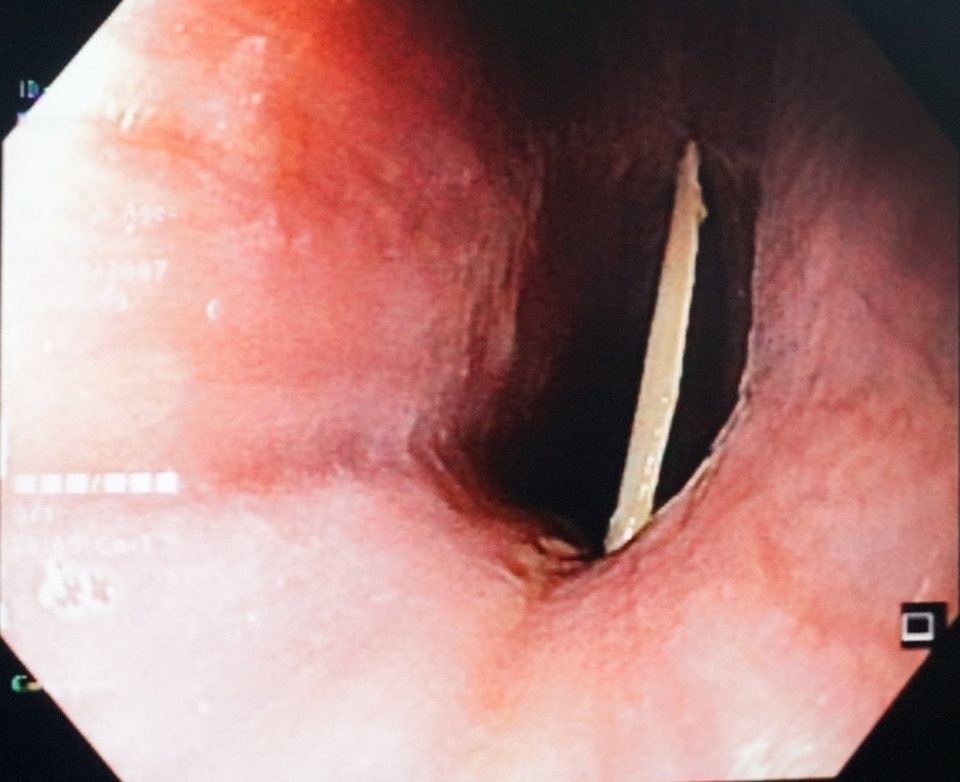

Tại bệnh viện, các bác sĩ đã chỉ định nội soi thực quản cho người bệnh. Kết quả cho thấy dị vật là mảnh xương gà bề ngang khoảng 2,5cm, có cạnh sắc nhọn nằm ngang cắm sâu 1/3 trên thực quản. Các bác sĩ đã tiến hành gắp dị vật ra bằng kìm chuyên dụng. Sau khi mảnh xương gà được gắp ra ngoài, cổ họng ông dần hết cảm giác đau rát, khó chịu.

Bác sĩ đã nội soi, gắp thành công mảnh xương gà cho người bệnh